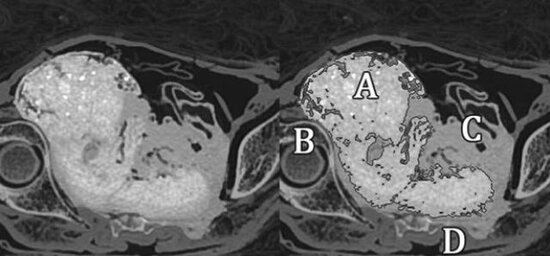

Elm adamları mumiyanın qarnını yoxlayanda döl tapıblar. 28 həftəlik (7 aylıq) olduğu bildirilən dölün tam 2000 yaşında olduğu məlum olduqdan sonra arxeoloqlar dərhal bunun səbəbini araşdırmağa başlayıblar.

Ananın mumiyalandığı zaman körpənin olduğu nahiyədə duzlama aparıldığı və dölün 2000 il qadının bətnində toxunulmaz qaldığı müəyyən edilib. Qadının necə öldüyü hələlik məlum deyil.